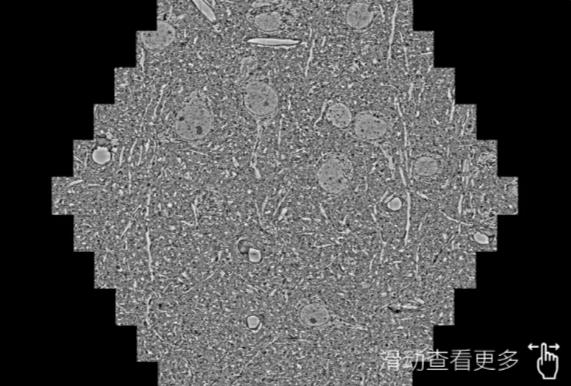

鼠脑切片。左图使用璧山蔡司璧山扫描电镜MultiSEM706对165μmx143pm面积区域成像,耗时仅需1.5秒。右图为鼠脑切片中30μm区域放大效果。样品由芝加哥大学B.Kasthuri提供。